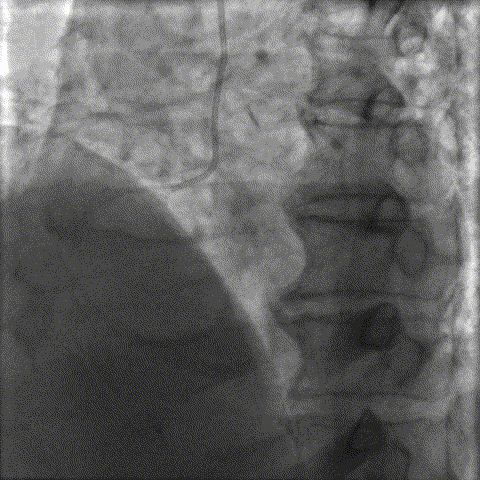

6FEBU3.5,Corsair微导管,Sion blue,FielderXTA

导丝通过后,微导管无法通过

更换Emerge 1.2/12球囊,仍无法通过

送入Telescope™ 导引延长导管,Sprinter2.0/20球囊轻松通过,成功预扩张

CuttingBalloon 2.0/10充分预处理

DCB 2.0/31  DCB2.5/20

LCX结果